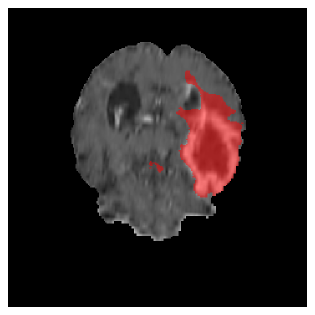

Appendix A Qualitative results

Figures 4 and 5 present the segmentation results for a patient from the BRATS dataset, visualized on a randomly selected slice. Figure 4 illustrates how tumor segmentation evolves over multiple episodes in S1 across different approaches including cumulative, naive, our approach, and the best buffer-free strategy (SI, =2). The cumulative approach, which trains on all encountered datasets together, maintains segmentation consistency across episodes but introduces significant amounts of false positives, particularly in the upper left area of the brain images. These misclassifications highlight its inability to generalize well across datasets despite access to all previous data. The naive approach, which learns sequentially without any continual learning strategy, suffers from severe catastrophic forgetting. While it initially segments well, performance deteriorates over episodes, leading to a near-complete loss of segmentation capability by the final episode. The SI (=2) approach, a regularization-based buffer-free CL strategy, performs reasonably well in early episodes but shows a significant performance decline over time. By the last episode, much of the tumor was no longer segmented, indicating difficulty in retaining prior knowledge. In contrast, our proposed approach initially produces more false positives but progressively refines its segmentation. By the final episode, it accurately retains the tumor region while minimizing misclassifications, demonstrating strong knowledge retention and adaptability across episodes. This suggests that our approach effectively mitigates catastrophic forgetting while maintaining segmentation performance over sequential learning.